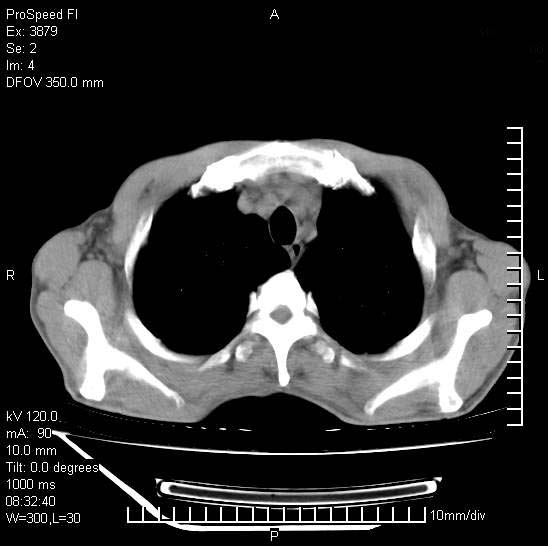

以下是引用37度在2008-6-6 11:20:00的发言:[br]1.包裹性积液,多考虑结核性;[br]2.穿刺术后改变。